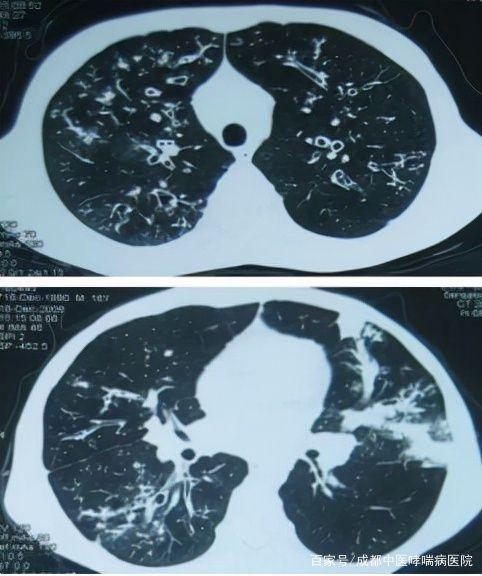

支气管扩张治愈不敢想?错!|咯血|气道|症状|治疗|杵状

支气管扩张图片

支气管扩张的症状图片

支气管扩张的ct图解

支气管扩张x线表现